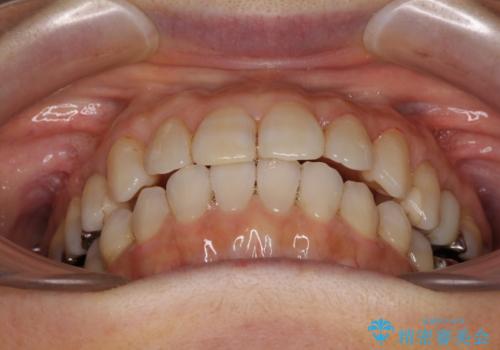

前歯の突出感と上下の隙間 インビザラインによる矯正治療

- 前歯の上下スペースと前歯の隙間を気にして来院された患者様です。

インビザラインにより上下の前歯の隙間を閉じながら、IPRを用いて口元の突出感を合わせて改善していくこととしました。

上下の隙間に舌が入り込むことが、すきっ歯やオープンバイトの原因であったため、舌の筋肉のトレーニングも並行して行い、後戻りの抑制を図りました。